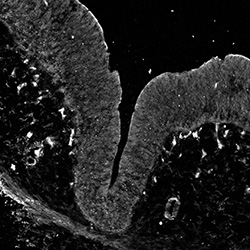

An anatomical analysis of the developing human midbrain from 6 post-conceptional weeks (PCW) to 22 PCW reveals increased tissue complexity, characterized by the emergence of dopaminergic nuclei, as highlighted by immunofluorescence analysis for tyrosine hydroxylase (TH).

DAPI

7PCW human midbrain

MAP2

SOX2

Merged